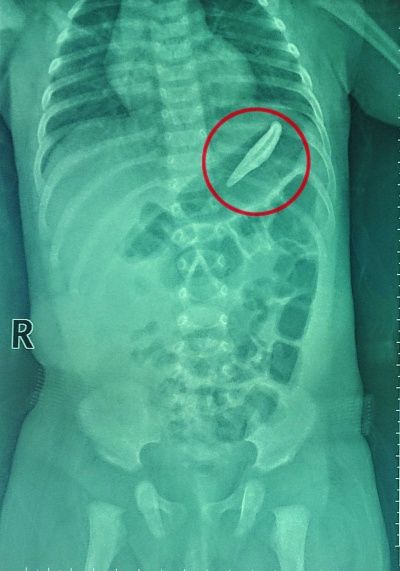

X光片下可以清晰地看到胃部的狗牙。

当地医院做X线检查后发现,那颗失踪的狗牙赫然就躺在小女儿的胃里!因为当地医疗水平有限,医生不敢取,徐女士一家赶紧找了辆车直奔南京市儿童医院。该院消化科刘志峰主任医师接诊后发现,由于消化道内的异物两头十分尖锐,加上材质比较滑,用胃镜取出难度较大,稍有不慎就可能损伤胃肠道。但是如果不及时处理,异物就成了“定时炸弹”。异物堵塞可能引起胃肠道嵌顿,尖锐的两头有可能导致胃肠道贯通伤,破裂穿孔的话就十分危险了,甚至需要开腹进行急诊外科手术。

面对心急如焚的徐女士和家人,刘志峰主任医师权衡之下,决定还是冒险为徐女士的小女儿进行胃镜取异物手术。6月16日上午10点30分,在做好充分的准备后,手术正式开始。刘志峰主任医师用胃镜配合异物钳小心翼翼地夹住长长的狗牙,顺着宝宝的消化道一点一点往外挪动,避免狗牙两端的尖锐部分与胃肠道接触。整个过程持续了一个多小时,异物终于被取了出来。真正看到这颗足有5厘米长的锋利牙齿,胃镜室的医生们也都是倒吸一口凉气。